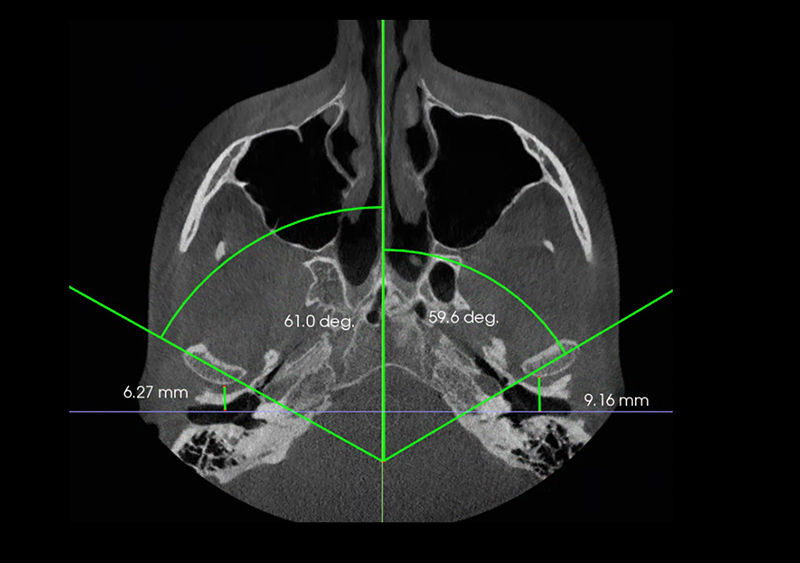

Exámen de Via Aérea Volumetría

Mediante el CBCT podemos analizar la vía aérea en toda su extensión tanto anteroposterior como lateral,

Lo que nos permite evaluar factores de riesgo para desarrollar OSA y predictibilidad de algunos tratamientos